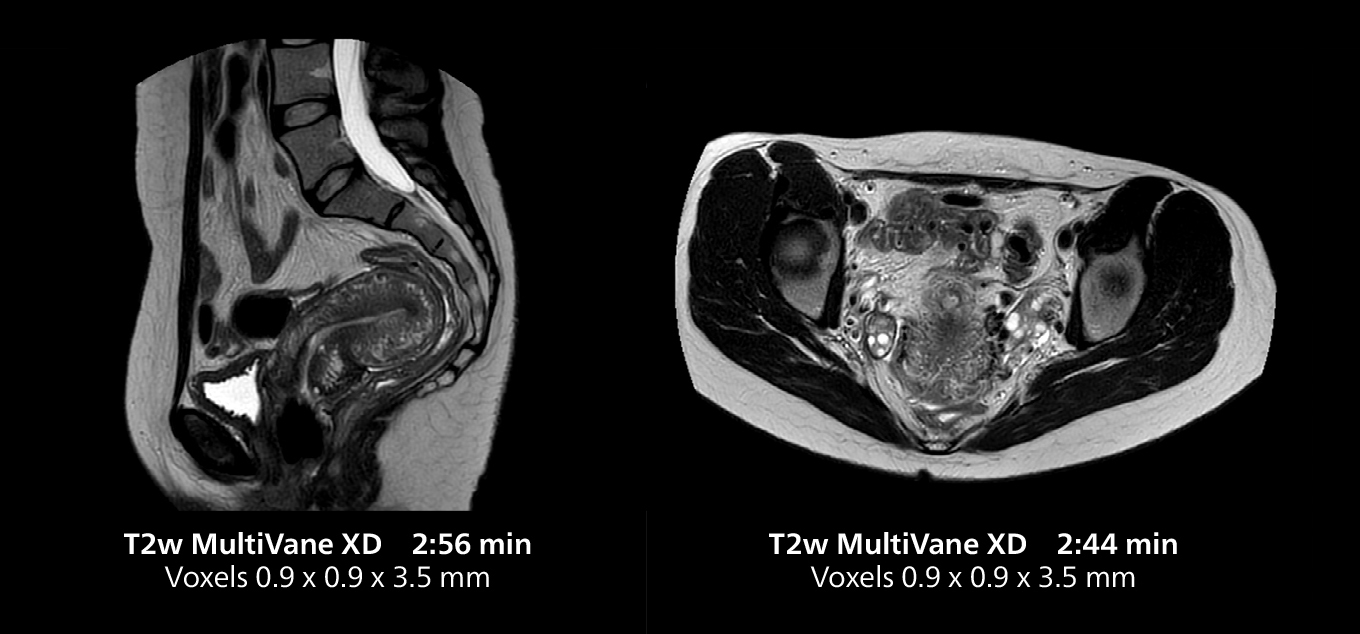

The isotropic high resolution 3D sequence in this MRI case allows for reformatting to obtain other orientations with high quality. Acquired on the MR 5300 system.

Dr. Gellée highlights the robust free-breathing scans as “the feature that makes the biggest difference in my daily work. The 3D free breathing sequences are very reproducible, and the axial acquisition is very good. For example, in endometriosis, which is one of my focus areas, it provides high contrast and good resolution so that I can see small details. We also use free breathing for liver and pancreas imaging. In multi-phase liver studies, 4D Free Breathing delivers 3-second temporal resolution, making a dynamic scan with more than one arterial phase possible.”

This MRI case illustrates good resolution and imaging quality obtained within reasonable scan times using the MR 5300 1.5T system with the anterior torso cardiac coil that allows use of a large field of view (FOV).